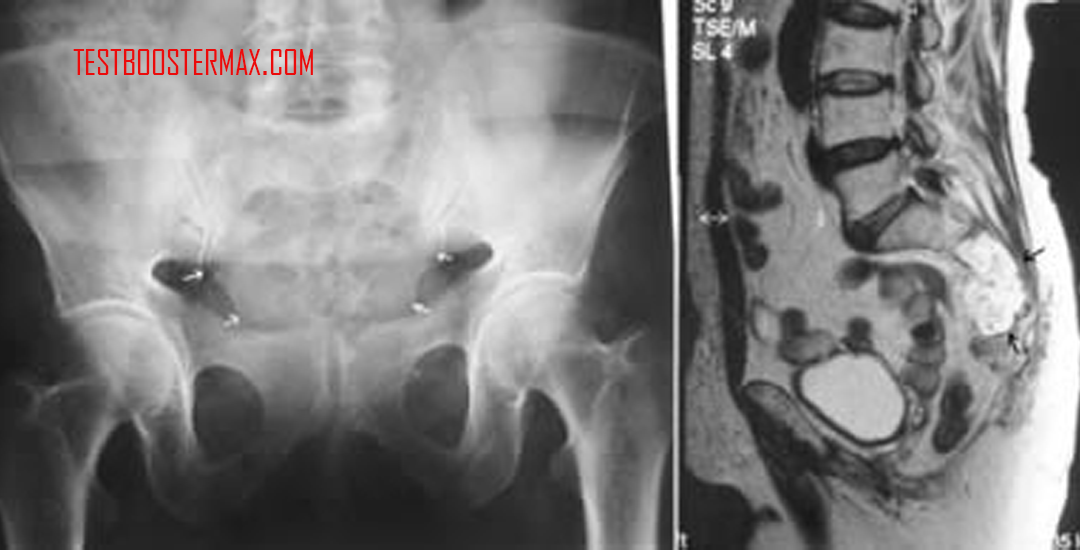

Imaging seperti MRI dan CT scan untuk menentukan lokasi dan ukuran tumor.

Biopsi jaringan untuk memastikan jenis kanker dan mengidentifikasi sel tumor secara histopatologi.